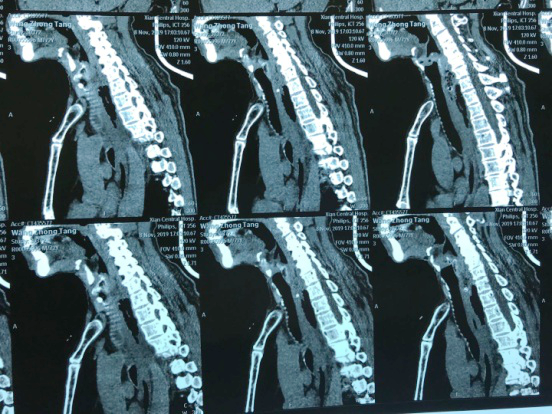

“大夫,快,我这人卡枣核5天没吃饭了,县医院说枣核又往下掉了”,2019118日下午,一位72岁老人在一群家属的搀扶下来到91论坛 耳鼻喉科门诊,门诊医师刘飞接诊患者询问病史,原来老人在村里“坐席”不慎将枣核误吞,在村卫生室、县城医院等多家医疗机构就诊,未能取出枣核,考虑枣核位置不断下移,建议转上级医院。至此患者因咽痛无法下咽已经5天滴水未进。患者既往糖尿病、冠心病,且未规范药物治疗,基础条件很差。考虑患者病情危重,予以迅速办理入院。权博源主任医师和尹黎波主治医师详细询问病史及查体后,为患者急查血:白细胞22,血糖、血酮、尿酮高,凝血象报危急值。患者食道异物食道穿孔合并严重感染,长期饥饿合并高血糖,手术风险很大。权博源主任医师亲自为患者制定治疗方案,立即抗感染、补液治疗,请内分泌科协助降糖降酮治疗,同时复查CT确定枣核现在位置,指标控制后立即手术。晚上10点,在麻醉科、手术室紧张有序的配合下,终于将枣核和覆盖在上方的鸡蛋样异物取出,术后患者平稳返回病房。